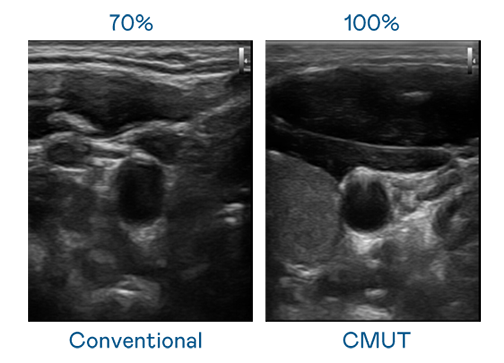

CMUT 技術是一種用電容式微機電元件來產生超音波訊號的技術。與傳統 PZT 壓電式技術相比,CMUT 頻寬增加 30%,更寬頻的超音波訊號讓影像解析度大幅提升,是實現高影像品質醫療超音波掃描、促進精準醫療發展的關鍵技術。

大頻寬帶來超清晰影像

超音波影像的解析度高低,首先取決於探頭能發出的訊號頻寬。AG官网 CMUT 可提供高清晰的超音波訊號,提供高頻寬、高靈敏度、影像紋理細節更高的超音波影像,協助醫護人員縮短影像判讀時間及利用精準的醫療影像進行診斷。